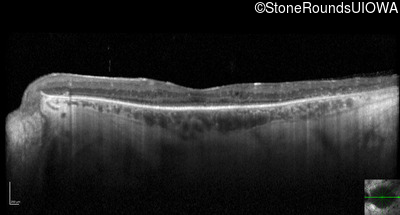

Optical Coherence Tomography - Right - 20/32 -2

Exemplar / OCT Stack

OCT Stack